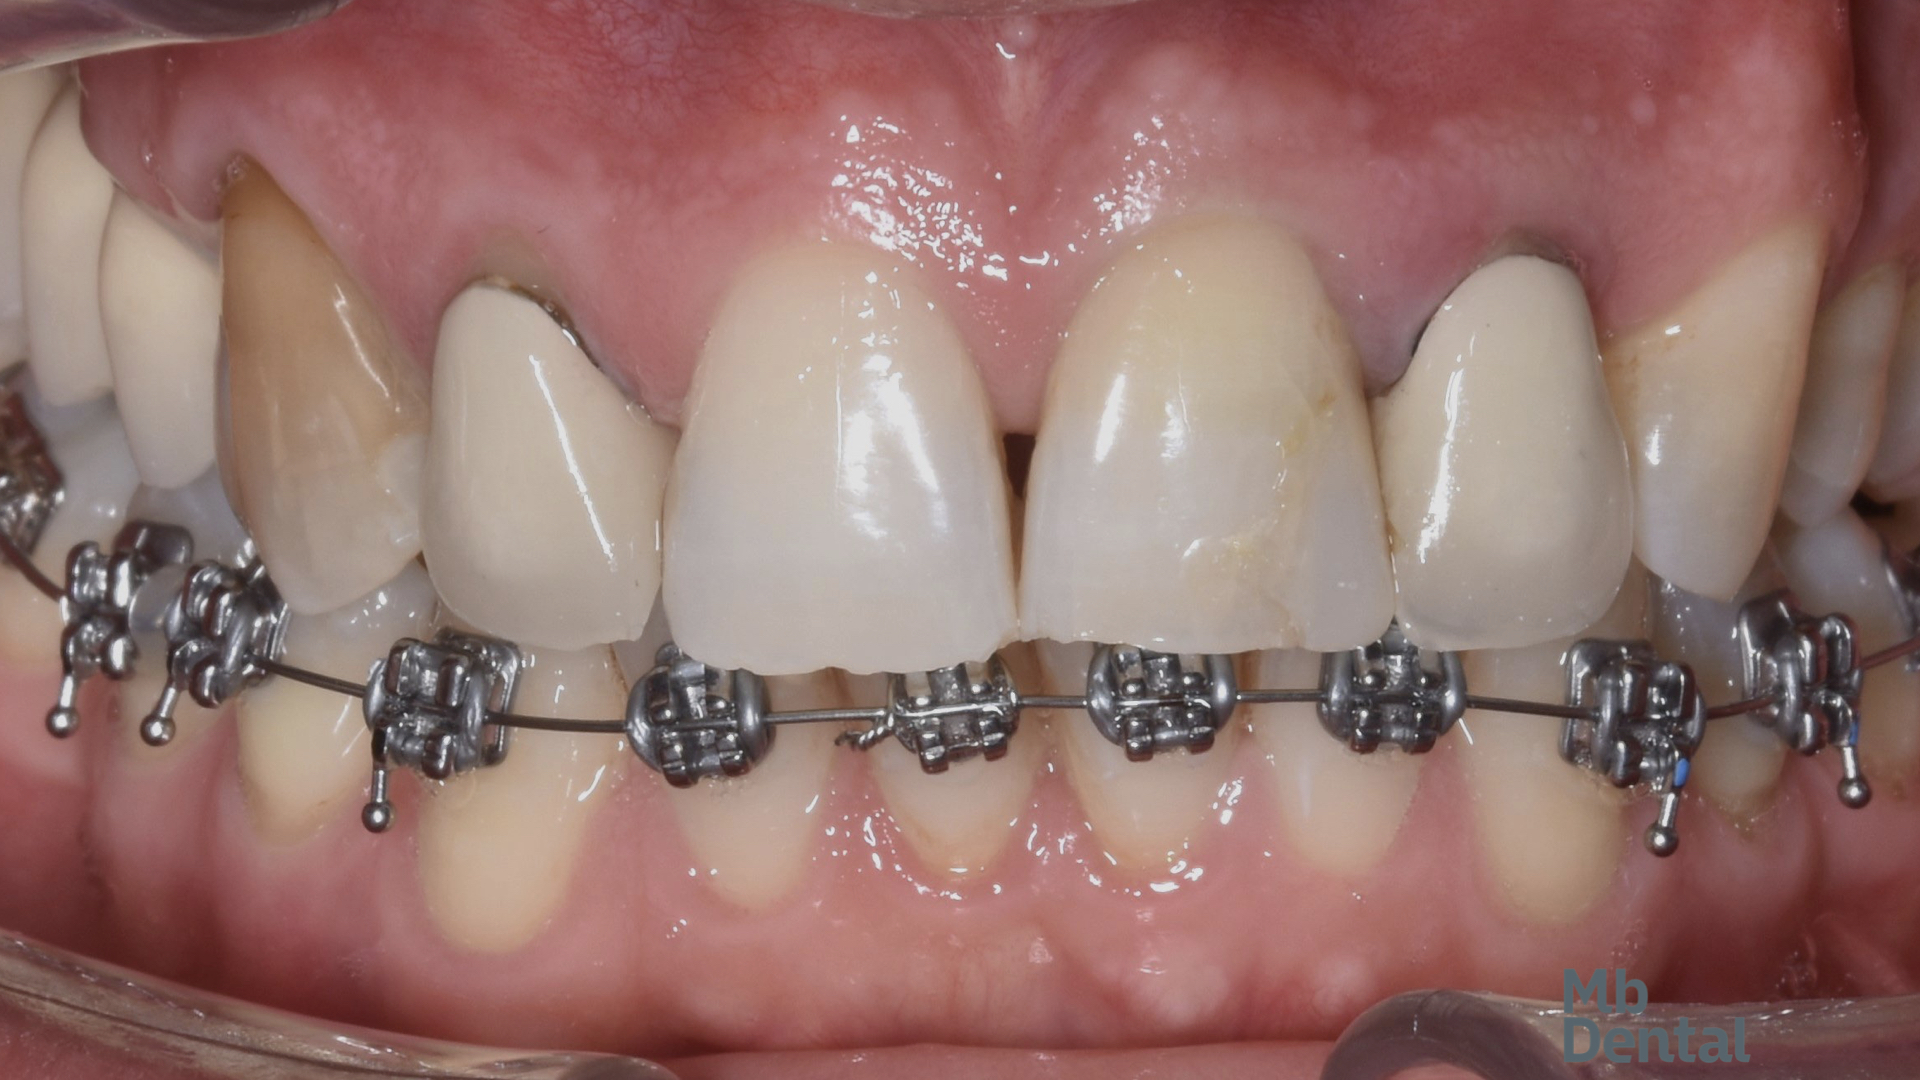

Inițial, la arcada inferioară a fost rezolvată inghesuirea dentara frontala si s-a creat spațiu pentru inserarea unui implant deoarece un molar a fost extras in trecut iar dinții vecini au migrat parțial. La nivelul dintilor superiori a fost necesara extractia unui incisiv lateral tratat endodontic a carei rădăcina s-a fracturat. Acesta a fost de fapt si unul dintre motivele care a motivat pacientul sa solicite o reabilitare complexă.

S-a realizat inserarea unui implant imediat postextractional protezat cu o coroana provizorie. Deoarece o parte dintre dinții anteriori au fost in trecut tratați endodontic iar coroane lor au suferit modificări de culoare si tratamentul protetic final a inclus coroane din ceramica pe zirconiu pe acești dinți iar singurul incisiv care era vital a primit o fateta ceramica.